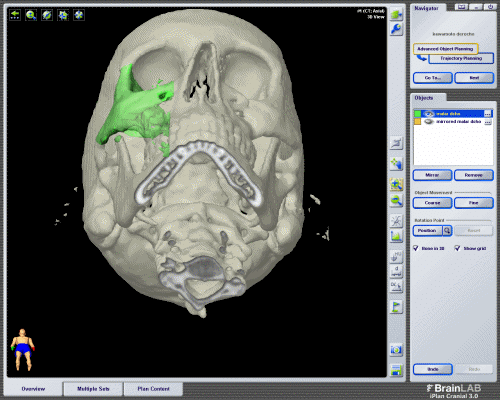

Planificación 3D reconstrucción órbita

En la mayoría de los casos el tratamiento consistirá en la extirpación del tumor. En MAXILOFACE aplicamos técnicas quirúrgicas poco invasivas que permiten una rápida recuperación del paciente y un buen resultado estético. El Dr. Néstor Montesdeoca es pionero en España en la utilización del neuronavegador para la localización del tumor de órbita y su extirpación sin comprometer estructuras vitales para la visión.

Empleamos de forma rutinaria planificación 3D y prótesis a medida para la reconstrucción de la órbita.